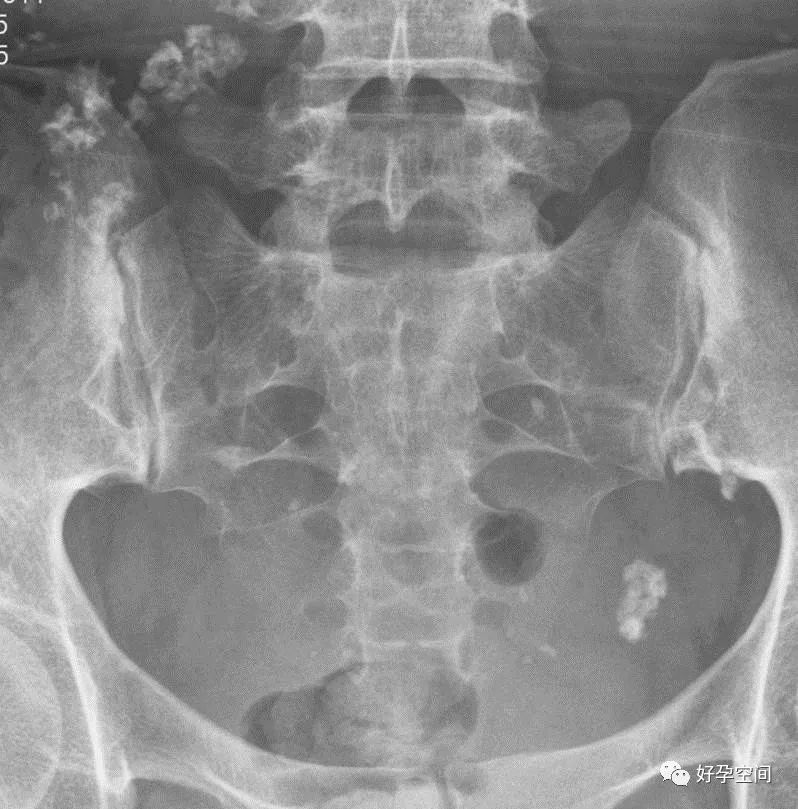

5、盆腔陈旧性结核钙化灶

盆腔内见多个片状及点状高密度钙化影